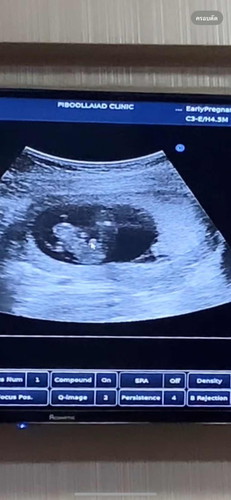

จากภาพน้องมีจู๋ใช่ไหมคะ ตอนแรกป้าหมอบอกว่าลูกสาว มารอบสองป้าหมอบอกจู๋โผล่ เราแอบนอยนิดนึงอยากได้ลูกสาว🥹

ถ้าซาวด์ตอนอายุครรภ์น้อย ได้ลูกสาว พออายุครรภ์มากขึ้น เป็นลูกชาย ปกติค่ะ เพราะอวัยวะเพศชายจะเจริญเติบโตช้ากว่าของเพศ ญ จะดูเพศชัวร์ๆต้องรอน้องประมาณหกเดือนค่ะ